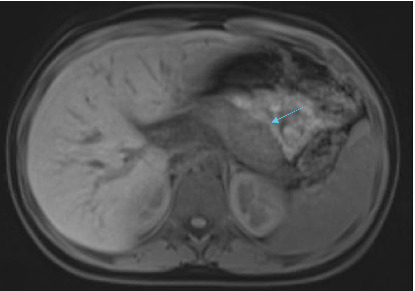

Abstract Image